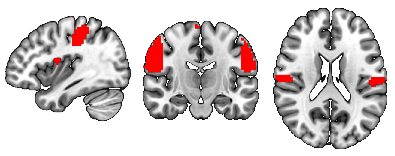

To identify the top ROIs for the intelligence prediction tasks, we first extracted the pooled ROIs after passing through the first layer of TopK Pool layer of a fully trained model using a holdout test set. We then selected the ROIs with highest frequency across each of the samples for all the intelligence scores. For fluid intelligence, we selected two ROIs (Middle Temporal Gyrus, and Middle Frontal Gyrus) (Fig 2(a)) with 90% frequency threshold. Similarly, for crystallized intelligence, middle frontal gyrus and caudate were selected with a frequency threshold of 90% (Fig 2(b)). For total composite scores, as the pooling ratio from hyper-parameter tuning was higher (0.78), we were able to extract 21 brain regions for 95% frequency. We categorized the selected regions into seven connectivity networks and plotted them independently in Fig. 3.

Refer to caption

(a) Middle frontal gyrus and Middle temporal gyrus

(b) Middle frontal gyrus and Caudate

Figure 2: Regions Significant in Fluid and Crystallized Intelligence Prediction

The top two regions contributing to fluid intelligence are the middle frontal gyrus and the middle temporal gyrus. In fact middle frontal gyrus contributes to all three intelligence scores, and its overall significance in predicting intelligence is in line with the literature. In particular, the dorsolateral prefrontal cortex in the middle frontal gyrus is well known to play a crucial part in many domains of cognitive processes, including working memory (Barbey et al. (2013)), attention control (Knight et al. (2020)), executive function (Nejati et al. (2021)), and decision making (Patterson et al. (2007)), etc (Yu et al. (2022)). Given its multi-domain involvement in cognition, this region’s engagement substantiates its relevance in all intelligence scores. The function of the middle temporal gyrus is relatively more specific to language relevant (Turken and Dronkers (2011)), such as semantic processing (Binder et al. (2009)), syntactic comprehension (Yu et al. (2022)), language comprehension, decoding intelligible speech. Its role in fluid intelligence prediction could be attributed to its contribution to information decoding and integration. In the context of crystallized intelligence, besides the middle frontal gyrus, caudate plays the most remarked contribution. The caudate’s association with learning (Choi et al. (2020)) and memory consolidation (Müller et al. (2017)) aligns with crystallized intelligence’s reliance on acquired knowledge and experience (Grazioplene et al. (2014)). The combined involvement of middle frontal gyrus and caudate suggests a cooperative engagement in translating stored knowledge into practical problem-solving skills, a hallmark of crystallized intelligence.